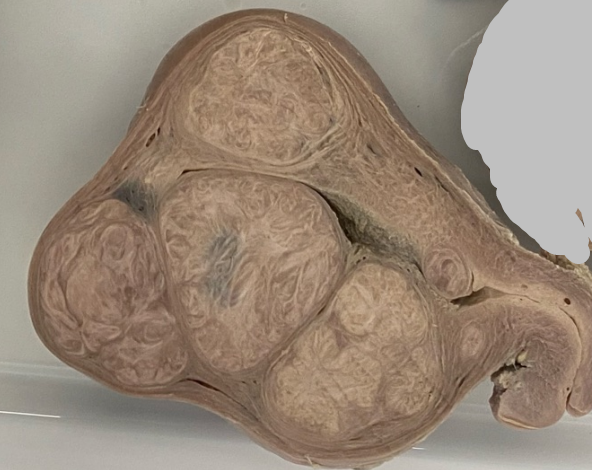

-Órgão: Rim.

-Descrição: Tamanho muito aumentado, pequenos

cistos externamente, que se evidenciam na superfície de corte, consistência esponjosa e múltiplos cistos.

-Diagnóstico: Doença policística renal da infância.